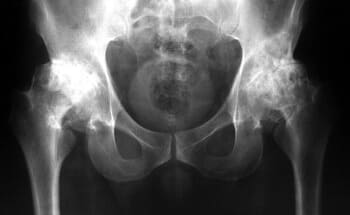

দুই বছর আগে আমি প্রথম আমার হাঁটু এবং নিতম্বে হালকা ব্যথা অনুভব করেছি। ব্যথা তীব্র ছিল না, তাই আমি এটিতে খুব বেশি মনোযোগ দিইনি... দেখা যাচ্ছে যে জয়েন্টের রোগগুলি খুব বিপজ্জনক এবং অবিলম্বে চিকিত্সা করা উচিত, আমার মতো অপেক্ষা করা উচিত নয়। একদিন আমার হাঁটুতে হালকা কিন্তু তীক্ষ্ণ ব্যথা হয়েছিল, এবং আমার নিতম্বের জয়েন্টটি গুরুতরভাবে আঘাত করতে শুরু করেছিল, এবং আমি ভেবেছিলাম যে কিছুই ভুল ছিল না, এটি চলে যাবে, যেমন এটি সাধারণত হয়। আমি ওষুধ ও মলম কিনে ব্যবহার শুরু করলাম। এক সপ্তাহ বা তার পরে, আমার অবস্থা তীব্রভাবে খারাপ হয়ে যায়, ব্যথা অসহ্য হয়ে ওঠে, আমার নিতম্বের জয়েন্টে তীব্র ব্যথা শুরু হয় এবং আমি প্রথমবারের মতো ডাক্তারের কাছে যাওয়ার সিদ্ধান্ত নিয়েছিলাম। তারা আমাকে একটি রোগ নির্ণয় দিয়েছে যা সস্তা ছিল না এবং আমার ডাক্তার পরীক্ষার ফলাফল দেখে আমাকে বলেছিলেন:

"আপনি আগে উপসর্গ উপেক্ষা কেন? আপনার অস্টিওআর্থারাইটিস আছে! অস্টিওআর্থারাইটিস, আপনি যদি অক্ষম হতে না চান তবে আপনাকে নিতম্ব এবং হাঁটু অস্ত্রোপচার করতে হবে!

এক কথায় আমি হতবাক! আমি আতঙ্কিত হয়েছিলাম, অপারেশনের জন্য আমার কাছে কোন টাকা ছিল না এবং আমি এর জন্য মোটেও প্রস্তুত ছিলাম না। জড়িত অর্থের পরিমাণ মহাজাগতিক ছিল... এবং আমি নিশ্চিত ছিলাম না যে আমি আমার বৃদ্ধ বয়সে এই ধরনের অপারেশন থেকে বাঁচতে পারব। আমি এর বিরুদ্ধে সিদ্ধান্ত নিয়েছি এবং তাকে আমাকে ওষুধ দিতে বলেছি।